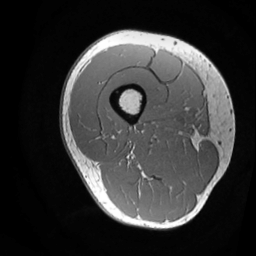

(a) Image

Finally, we define the set of corrected pseudo-labels as the intersection between the and masks. Examples are shown in Fig. 2.

Inspired by source-free domain adaptation approaches [8], we argue that the feature within the same category should lie closer to their class prototypes, enforcing a high correlation for samples of the same class. In the case of segmentation, image regions with highly correlated voxels in feature space often have compact intensity ranges [18]. Thus, instead of estimating the distance of a pixel to different class prototypes [13], we directly exploit the class prototype information hidden in the intensity distribution of a set of given regions. As the intensity values of the thigh muscle are mostly distributed in the range of after normalizing the input images () to the range , we extract coarse masks that exclude most of the IMF tissue. A single coarse mask is denoted as: